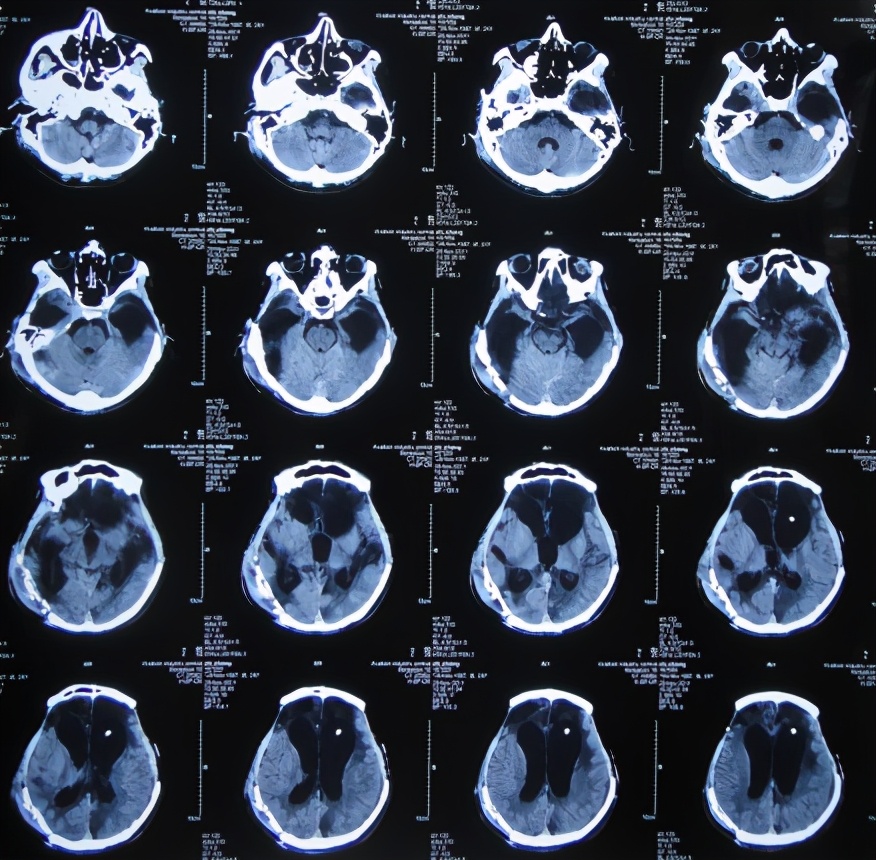

患者于2011年1月14日晚11点,意外发生车祸当即昏迷,120救护车将其送往第1家的安徽省合肥市的某三甲医院,查头颅CT:重度颅脑损伤,脑出血( 图-1 )。

图-1: 2011年1月15日头颅CT